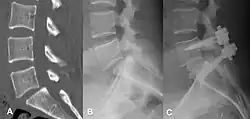

(A) CT sagittal view of a low grade slip.

(B) Lateral radiograph pre-operative intervention.

(C) Surgically treated with L5–S1 decompression, instrumented fusion and placement of an interbody graft between L5 and S1.

Both minimally invasive and open surgical techniques are used to treat anterolisthesis.[49]